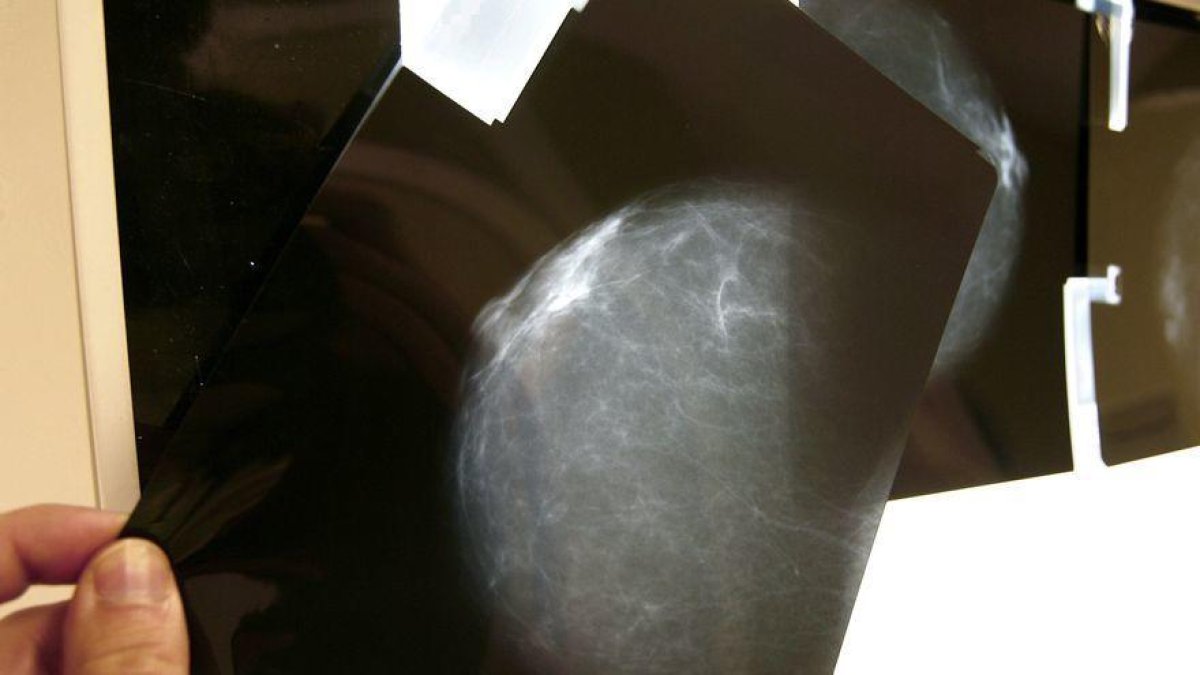

Una mutua privada ha indemnizado con 140.000 euros a una mujer por el retraso en el diagnóstico de un cáncer de mama, después de un acuerdo entre las partes. La paciente presentó episodios de secreción hemorrágica a través del pezón durante febrero del 2016, cuando estaba embarazada, e informó a su ginecólogo. Los especialistas no le hicieron una mamografía asegurando que podía comportar un riesgo para el feto. Un año después, se le diagnosticó un carcinoma infiltrando en el pecho. Este retraso en el diagnóstico ha comportado un tratamiento más radical y la extensión de la enfermedad hasta metástasis, según ha informado el Defensor del Paciente, asociación a la que está adscrita la letrada de la demandante.

Esta asociación ha recordado que existe reiterada literatura científica que defiende que un feto puede tolerar la poca cantidad de radiación emitida en una mamografía, sin que eso comporte ningún riesgo.

Añade que la mujer tenía importantes antecedentes oncológicos familiares, así como una clínica reiterada de hemorragias a través de los pezones. Por eso, defiende que no se tendrían que haber escatimado las pruebas necesarias, ni posponerlas para que estuviera embarazada o, más tarde, dando el pecho a su hijo. Argumenta que aquello que era prioritario era hacer un diagnóstico precoz o, como mínimo, advertir a la paciente de los riesgos que corría si este no se hacía.